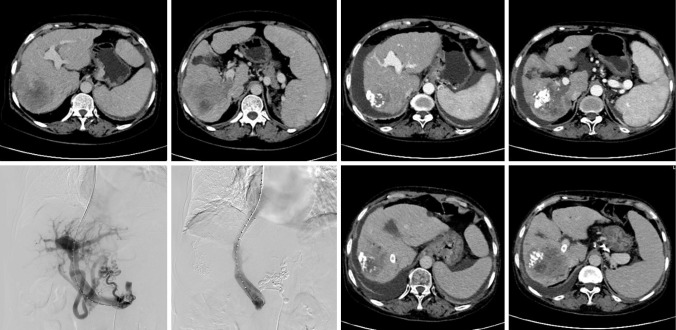

Methods: In this retrospective study, 21 patients with HCC complicated with PHT who were admitted to The Second Hospital of Nanjing between June 2018 and June 2023 were included. TIPS was performed, and liver and kidney function, blood routine, and biochemical indicators such as ammonia were examined preoperatively, at 1 week postoperatively, and at 1 month postoperatively. To determine the improvements in stent blood flow, ascites, and esophageal and gastric varices, ultrasound and/or enhanced computed tomography were performed. Treatment was evaluated based on the Modified Solid Tumor Efficacy Evaluation Criteria. Parameters such as portal vein pressure and portal blood flow before and after TIPS were analyzed using paired-sample t-tests.

Results: Postoperatively, the direct pressure of the portal vein of patients decreased significantly from 28.33±7.15 to 19.27±3.10 mmHg (P<0.05). The amount of ascites also significantly decreased, whereas esophageal and gastric varicose veins significantly improved. Meanwhile, no significant differences were observed in liver or kidney function indicators, including bilirubin, transaminase, and creatinine, from the preoperative to the postoperative period.

Conclusions: TIPS can effectively improve the various symptoms of PHT without increasing the incidence of liver function damage or other complications in patients with HCC complicated with PHT.